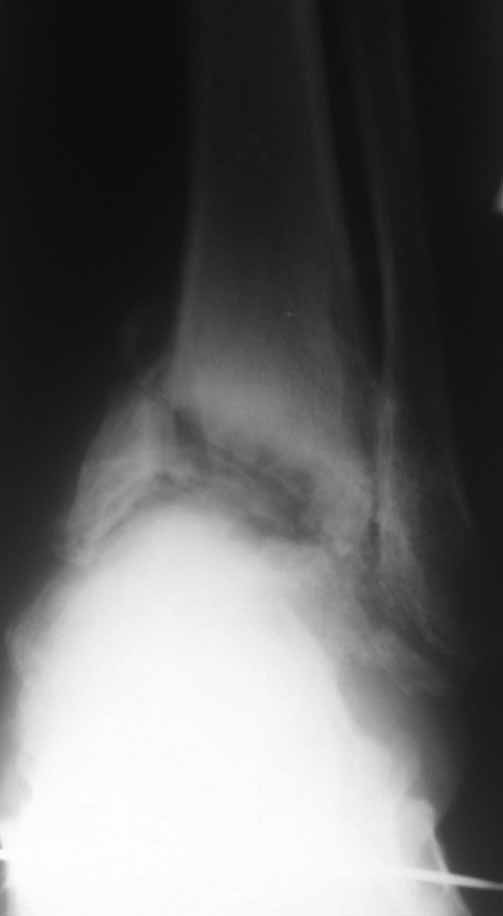

Зачем вытяжение - эффект на рентгенограммах виден.

Склоняемся к мысли, что все таки Charcot's Joint.

Планируем артродез стержнем правого голеностопа + аппарат на левый голеностоп.

Остается вопрос - как монтировать ? одномоментно корректировать или все таки постепенно аппаратом?